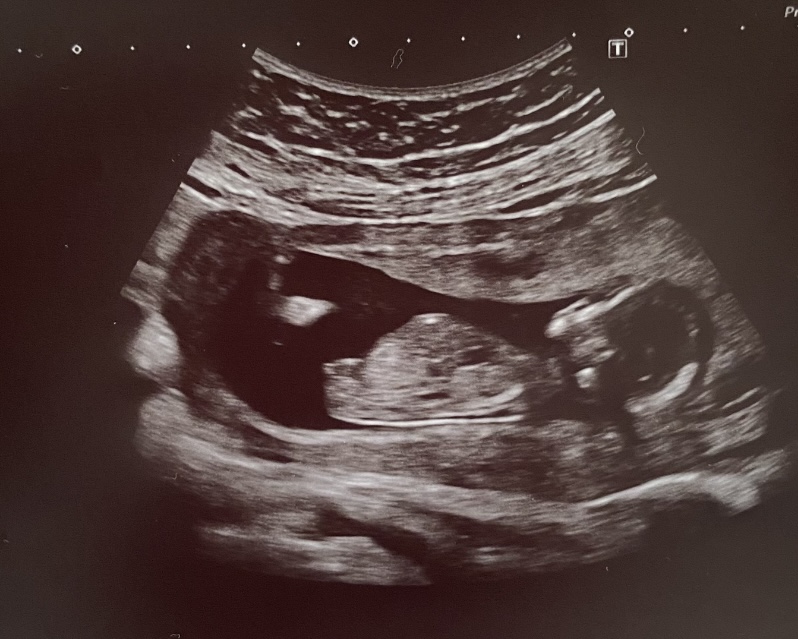

Hezky den, vcera jsem byla na kontrole u doktorky, jsem 15 tt a vse v poradku 🙂 Ptala se, jestli chceme vedet pohlavi a urcite chceme 🙂 Rikala, ze tam neco vidi a kdyby si mohla vsadit, tak na kluka. Doma mame malou cacorku, tak jestli se muzeme tesit na chlapecka, co myslite? 🙂 Fotku mame z prvniho sreeningu. Jistejsi to bude na dalsi kontrole. Moc dekuji.

@kar17 na fotce není vidět nikde pohlavní hrbolek, podle kterého by se to dalo určit. Pokud řekl dr kluka, asi to tak bude 🙂

@hela222 teda jestli to co tam je, je pohlavni hrbolek, tak teda holka podle me 🤷🏼♀️ ale ja nejsem doktorka 😄